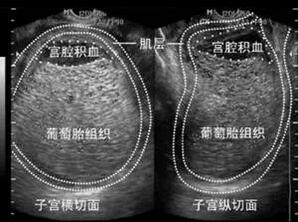

由于临床医生对于阴道出血、子宫增大且妊娠试验阳性的妇女多数怀疑为妊娠并发症,如先兆流产或稽留流产、异位妊娠,故详细确切的病史和全面的检查对妊娠滋养细胞疾病的正确诊断尤为重要。B超、MRI等影像学诊断也非常有价值,一般提示“宫腔蜂窝状改变”或“积雪征”。

图:B超提示完全性葡萄胎

多采用经阴道彩色多普勒超声检查,可检测到葡萄胎特征性超声表现。完全性葡萄胎的典型超声影像表现为:子宫明显大于孕周,宫内没有孕囊或胎心搏动,部分性葡萄胎有时可见胎儿或羊膜囊,但胎儿常合并畸形;侵润性葡萄胎通常表现为宫内1个或多个边界模糊的团块,含无回声区;绒毛膜癌表现为使子宫增大的不均质团块,这种不均质表现与坏死和出血区域对应,肿瘤可能会延伸到子宫旁组织;胎盘部位滋养细胞肿瘤表现为宫内胎儿可能存活,胎盘高回声团,团块通常侵及子宫肌壁。

(图:完全性葡萄胎超声图)